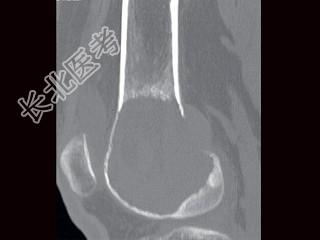

- 单项选择题男,24岁, 左大腿及膝部痛,结合图像, 最可能的诊断是 ( )

A、骨巨细胞瘤

B、骨囊肿

C、成软骨细胞瘤

D、动脉瘤样骨囊肿

E、骨肉瘤